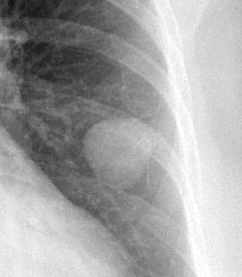

Gallery Congenital Hamartoma 1 PA c/u

Hamartoma 1 PA c/u